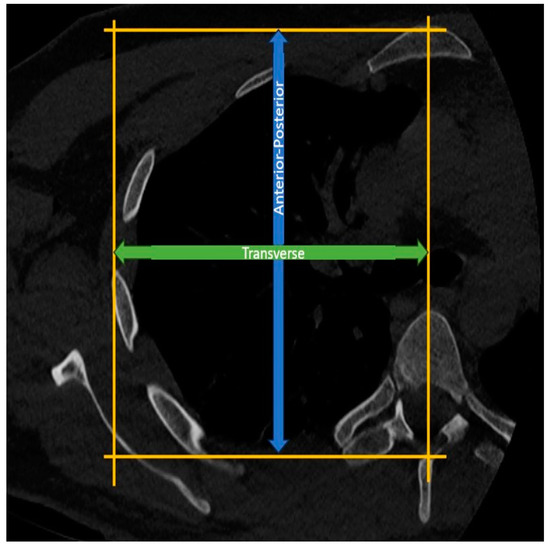

Measurement of Thoracic Anterior-Posterior Diameter: In the axial CT sections at the T4-5 level, the length between a line drawn parallel to the sternum from the anterior surface of the sternum and another line drawn parallel to this line from the apex of the spinous process of the corresponding vertebra is assessed as the thoracic anterior-posterior diameter (Figure 4).

Measurement of Hemithoracic Transverse Diameter: In the axial CT sections at the T4-5 level, a vertical line is drawn from the midline of the vertebra, connecting a line drawn parallel to the sternum from the anterior surface of the sternum and another line drawn parallel to this line from the lateralmost part of the corresponding rib. The distance between these lines is then assessed as the thoracic transverse radius (Figure 4).

The measurements of thoracic diameter were conducted based on morphometric standards employed in the literature by disciplines such as thoracic surgery and pulmonology [6]. The reason for standardizing the method to the T4-5 level was also based on the level of the scapular spine.

Figure 4. Measurement of anterior-posterior thoracic and transverse hemithoracic diameter.